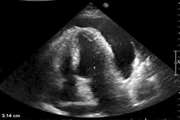

تجمع شدید مایع اطراف قلب به دلیل بیماری کبدی

یک مرد ۶۰ ساله ایرانی با سابقه هپاتیت خودایمنی و سیروز کبد، ناگهان با تنگی نفس شدید و درد سینه به اورژانس آمد – پزشکان متوجه شدند بیش از یک لیتر مایع اطراف قلبش جمع شده و قلب را تحت فشار مرگبار قرار داده است.